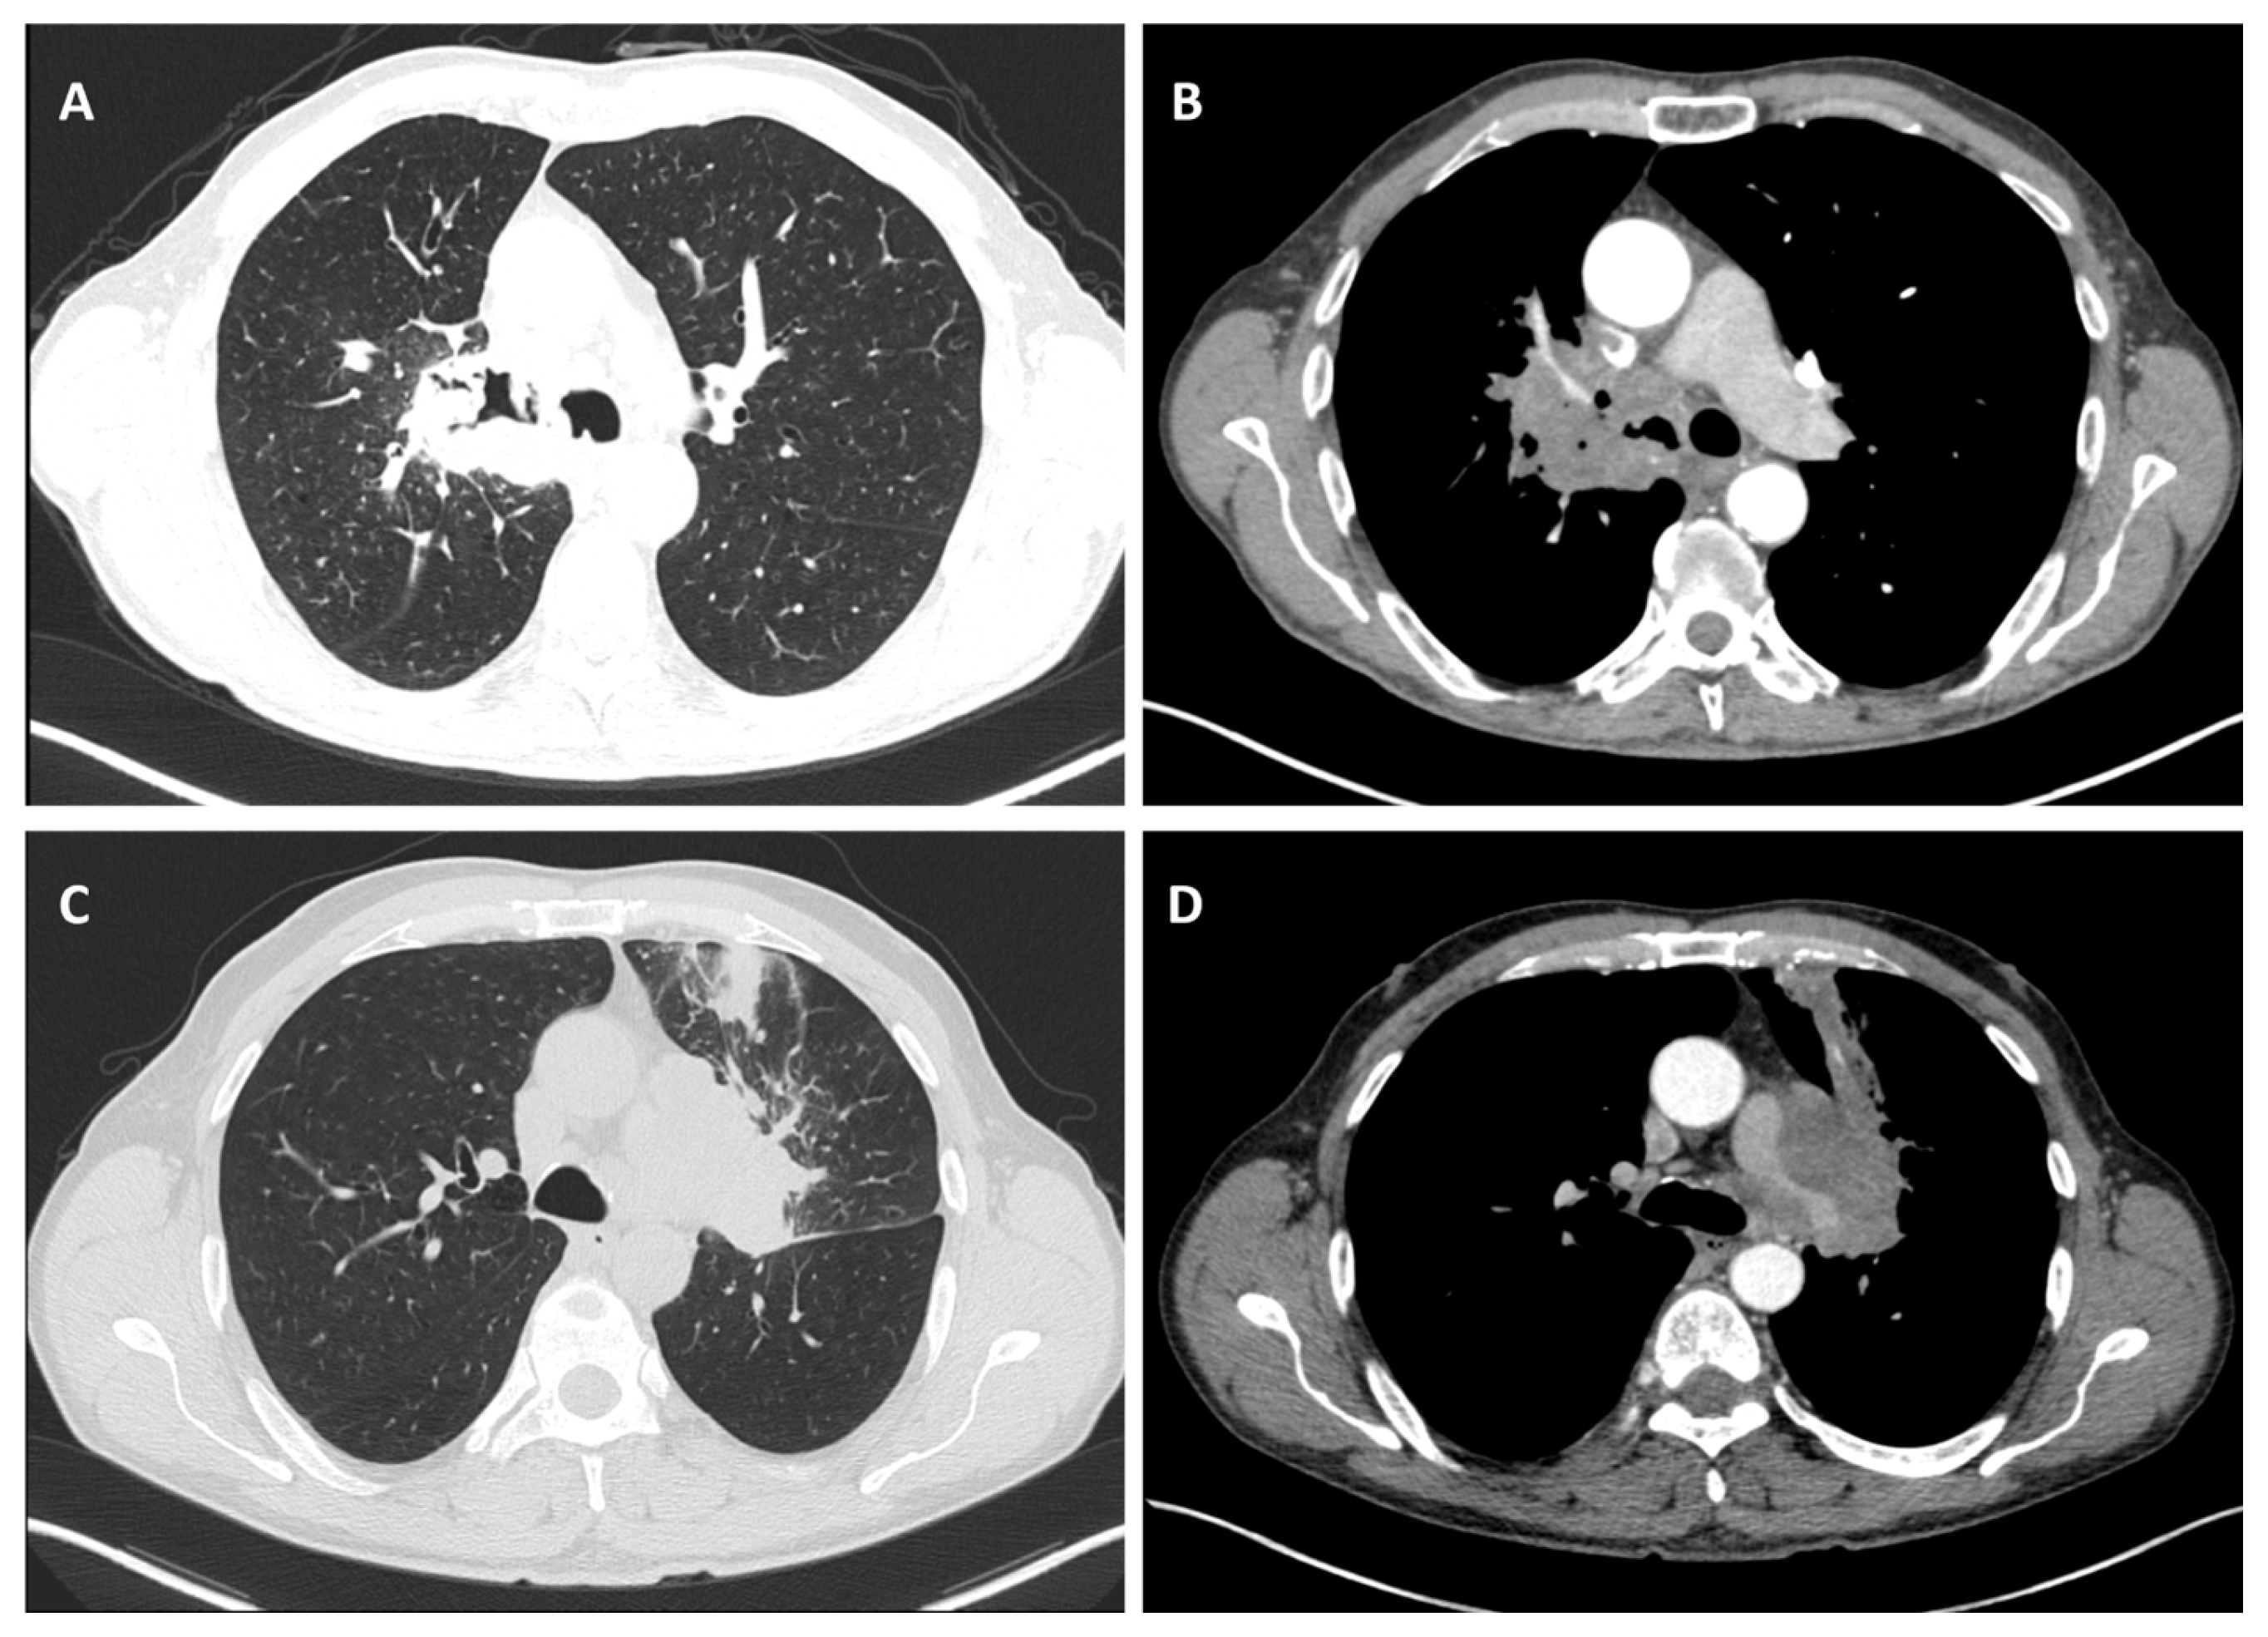

Considering the exclusion criteria previously mentioned, a total of 58 patients were analysed in this study, in which 26 cases were pathologically proven to be adenocarcinoma (Figure 1), 22 cases were shown to be squamous cell carcinoma (Figure 2), and 10 cases were shown to be small cell lung cancer (Figure 3).

Figure 2.

Axial CT of two different cases of squamous cell carcinoma: (A,B) show a right hilar mass with cavity and air bubbles inside, with invasion of the hilar vessels and right main bronchus extending over less than 2 cm from the carina; and (C,D) show a left hilar mass with atelectasis, necrosis, septal thickening, and important invasion of the pulmonary trunk and left pulmonary artery.